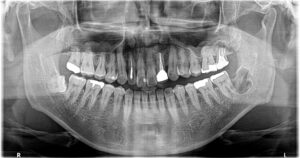

③左下嚢胞摘出後パノラマ。

①は根管治療のみでは治癒しなかったため歯根端切除術を約3か月前に行い歯冠補綴まで行っております。

②も同じくらいに根管治療(MTA根充)を行い歯冠補綴まで行っております。